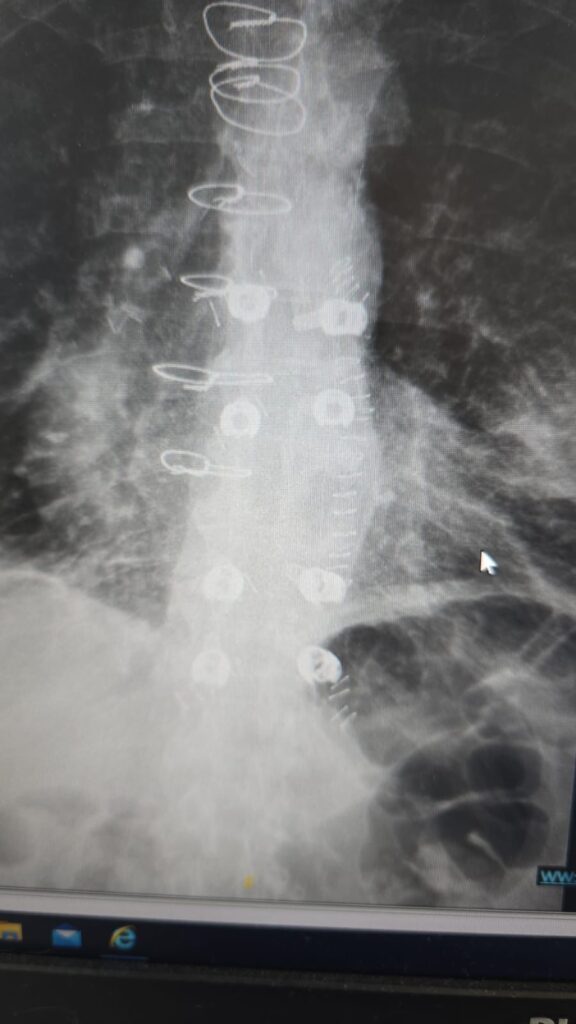

המטופל, גבר בן 60 שחלה בסרטן ריאה שפיתח גרורה בעמוד השדרה, הגיע למיון אסותא אשדוד כשהוא בסכנת שיתוק מיידית. במהלך הניתוח הוחדרו 8 ברגים ומוטות מקרבון בחיתוכים של כ־1 ס”מ בלבד, ובמקביל נכרת הגידול שגרם ללחץ על חוט השדרה. התוצאה הייתה דרמטית:

הטכניקה להכנסת ברגים בעמוד השדרה דרך חתכים זעירים אינה חדשה. למעשה, היא קיימת כבר כ־30 שנה ומשמשת בעיקר לטיפול בשברים בלתי יציבים. השיטה מבוססת על החדרת מחט לתוך החוליה בהנחיית שיקוף, הכנסת תיל מתכת עדין, הברגת הבורג למקומו המדויק, ולבסוף הכנסת מוט דרך אותם חתכים. השיטה מאפשרת ניתוח כמעט ללא דימום, זיהום מינימלי והחלמה מהירה.

ברגים ומוטות מקרבון אינם יוצרים הפרעות בהדמיות MRI, ומאפשרים לבצע בדיקות איכותיות גם לאחר הניתוח. בנוסף, הם מפחיתים משמעותית סיכונים בהקרנות-ומאפשרים לרופא האונקולוג לכוון את הקרינה בדיוק רב יותר.